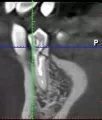

Зависит от того, насколько он треснул.

Если дефект распространился на корень зуба, то, однозначно, удалять.

Если корень целый, то необходимо извлечь штифт, изготовить культевую штифтовую вкладку и покрыть коронкой.